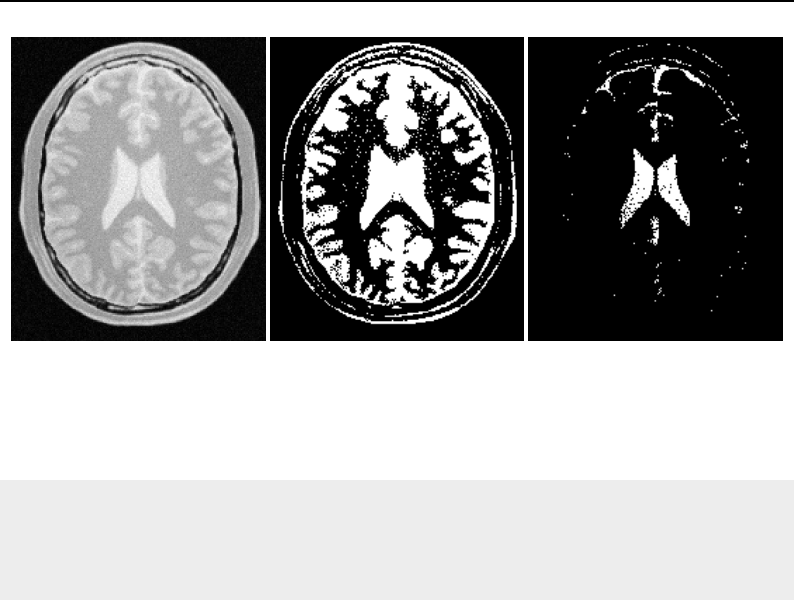

The National Library of Medicine Insight Segmentation and Registration Toolkit, shortened as the

Insight Toolkit (ITK), is an open-source software toolkit for performing registration and segmenta-

tion. Segmentation is the process of identifying and classifying data found in a digitally sampled

representation. Typically the sampled representation is an image acquired from such medical instru-

mentation as CT or MRI scanners. Registration is the task of aligning or developing correspondences

between data. For example, in the medical environment, a CT scan may be aligned with a MRI scan

in order to combine the information contained in both.